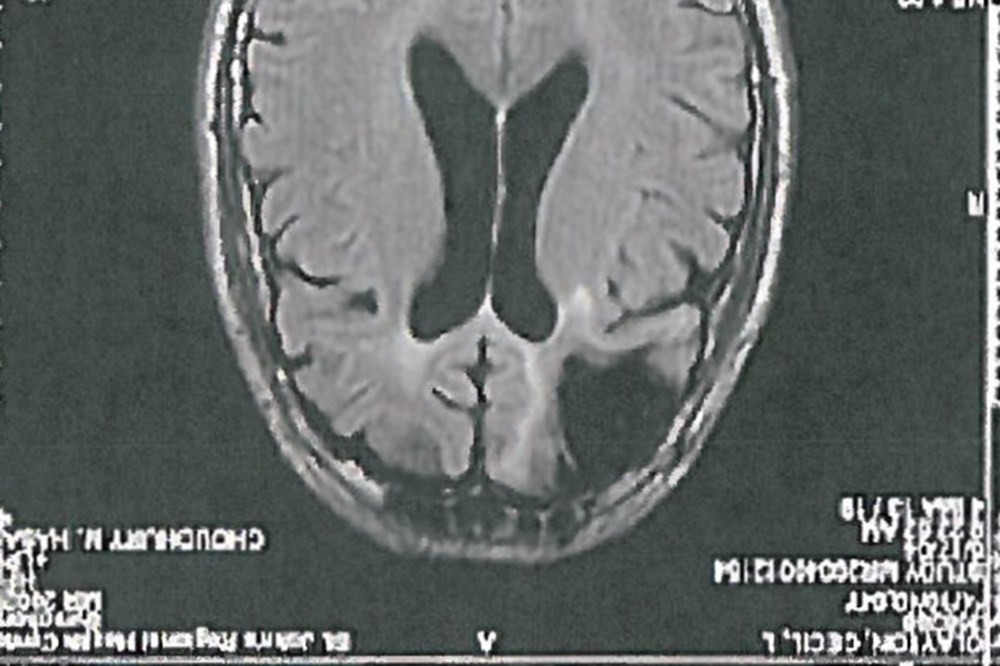

In 1972 — some 24 years before committing the crime for which he was sentenced to death — Clayton was injured in a sawmill accident in which a piece of wood pierced his skull. As a result, doctors removed one-fifth of Clayton’s frontal lobe, the part of the brain that controls decision-making, mood, and impulse-control. Thereafter, Clayton “broke up with his wife, began drinking alcohol and became impatient, unable to work and more prone to violent outbursts,” one of his brothers told The Atlantic. His IQ dropped, and in 1983, Clayton was diagnosed with chronic brain syndrome, a condition said to decrease mental function.